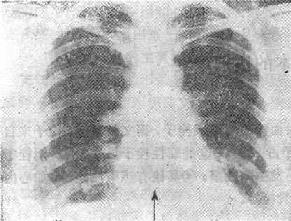

图116-1 肺梗死

(三)胸片可以显示肺栓塞的某些X线表现 ①一侧膈肌升高,大约有一半的急性肺栓塞的患者有此表现(肺容积的减少);②约有30%~50%的肺栓塞患者有一过性的肺实质浸润;③肺不张(约20%),但机制不清;④胸膜渗出,有1/3的患者出现;⑤有两个特异性的X线表现:Hampten’s驼峰征,为一个肺内的实变征,呈圆形圆顶状轮廓,顶部指向肺门,位于肺肋膈角区或后肋膈窦区;Wamptark’s征,栓塞侧近侧肺动脉扩张而远侧缺乏之灌注(无血管区),这两种特异的征象是很少见的;⑥肺动脉主干扩张、肺动段突出,甚至右心室增大。